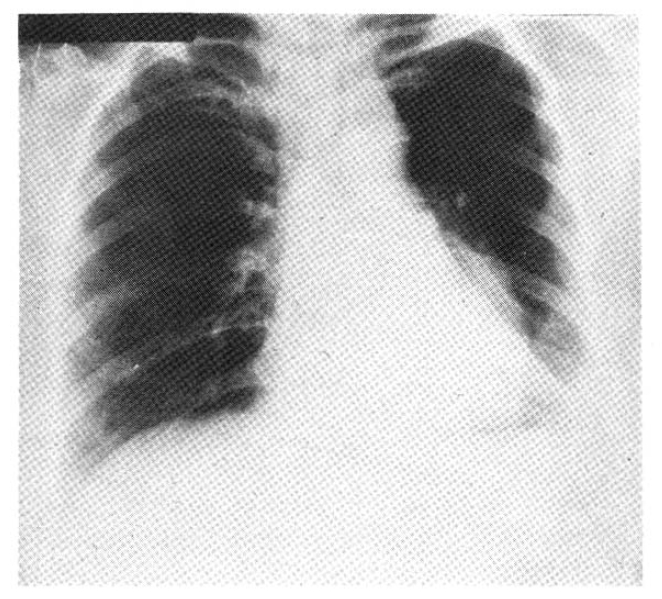

Fig. 4.

Computed tomogram of the chest showing left lower lobe collapse and aortic invasion from the tumor